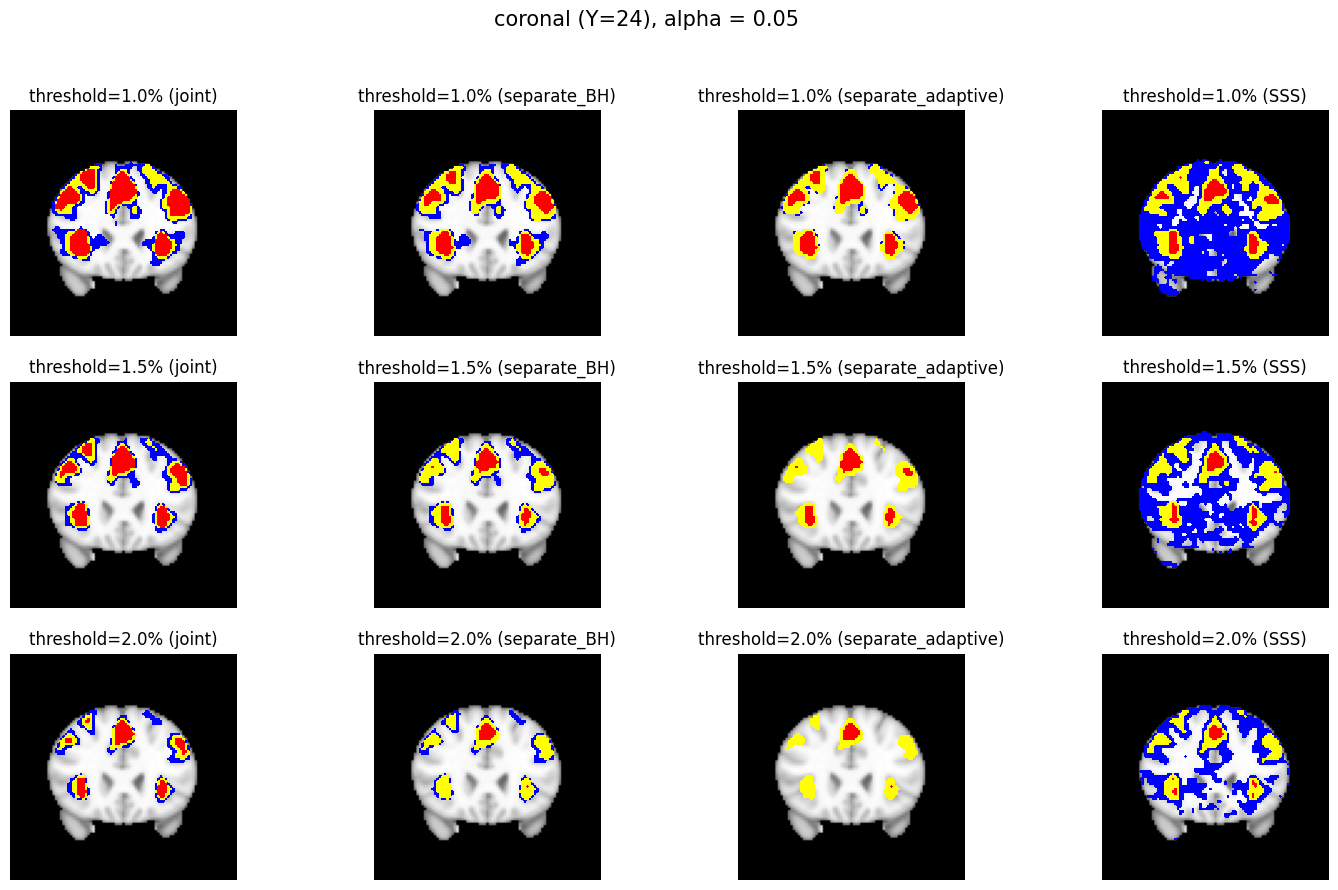

The confidence regions are constructed on fMRI scans from 77 subjects as a real data application of the proposed methods after applying additional smoothing with Gaussian kernel with FWHM to match the results shown in Bowring (2019) [BOWRING2019116187]. Confidence regions using 1) the joint method with , 2) the separate method with BH adjustment for upper and lower side each with , 3) the separate method with BH adjustment for upper side and two-stage adaptive procedure for lower with , and 4) SSS () were compared with threshold level 1.0%, 1.5%, and 2.0% Blood Oxygenation Level Dependent (BOLD) change. Joint control confidence regions are produced with instead of 0.05 for the reasons mentioned in chapter 3.

| Threshold | Joint | Separate (BH) | Separate (adaptive) | SSS |

|---|---|---|---|---|

| 1.0% |

|

| 1.5% |

| 2.0% |

For all slices, FDR controlling methods show tighter inference of both upper and lower CR compared to the SSS method. SSS shows smaller upper CR and larger lower CR which suggests more conservative inference compared to FDR controlling testing based methodologies. This is due to the fact that by controlling for FDR, the method allows for more false discoveries in exchange for more discoveries in general. Despite having higher level at , joint control confidence regions still show comparable results to other methods even with higher significance level. Naturally, as the threshold goes up, the area enclosed between the upper and lower confidence regions decreases.

Confidence regions with separate controls of FDR for lower and upper are presented in two forms for comparison: one with BH procedure for the lower confidence region, and the other one with the two-stage adaptive procedure for the lower confidence region. The upper confidence region remains the same as both methods uses BH procedure for the upper set FDR control. Lower confidence regions with adaptive method are smaller than lower sets with BH procedure which is to be expected as the two-stage adaptive procedure is less conservative when more voxels are thought to be rejected. In the context of negative one-sided testing, this is equivalent to when there are less number of voxels above than below .